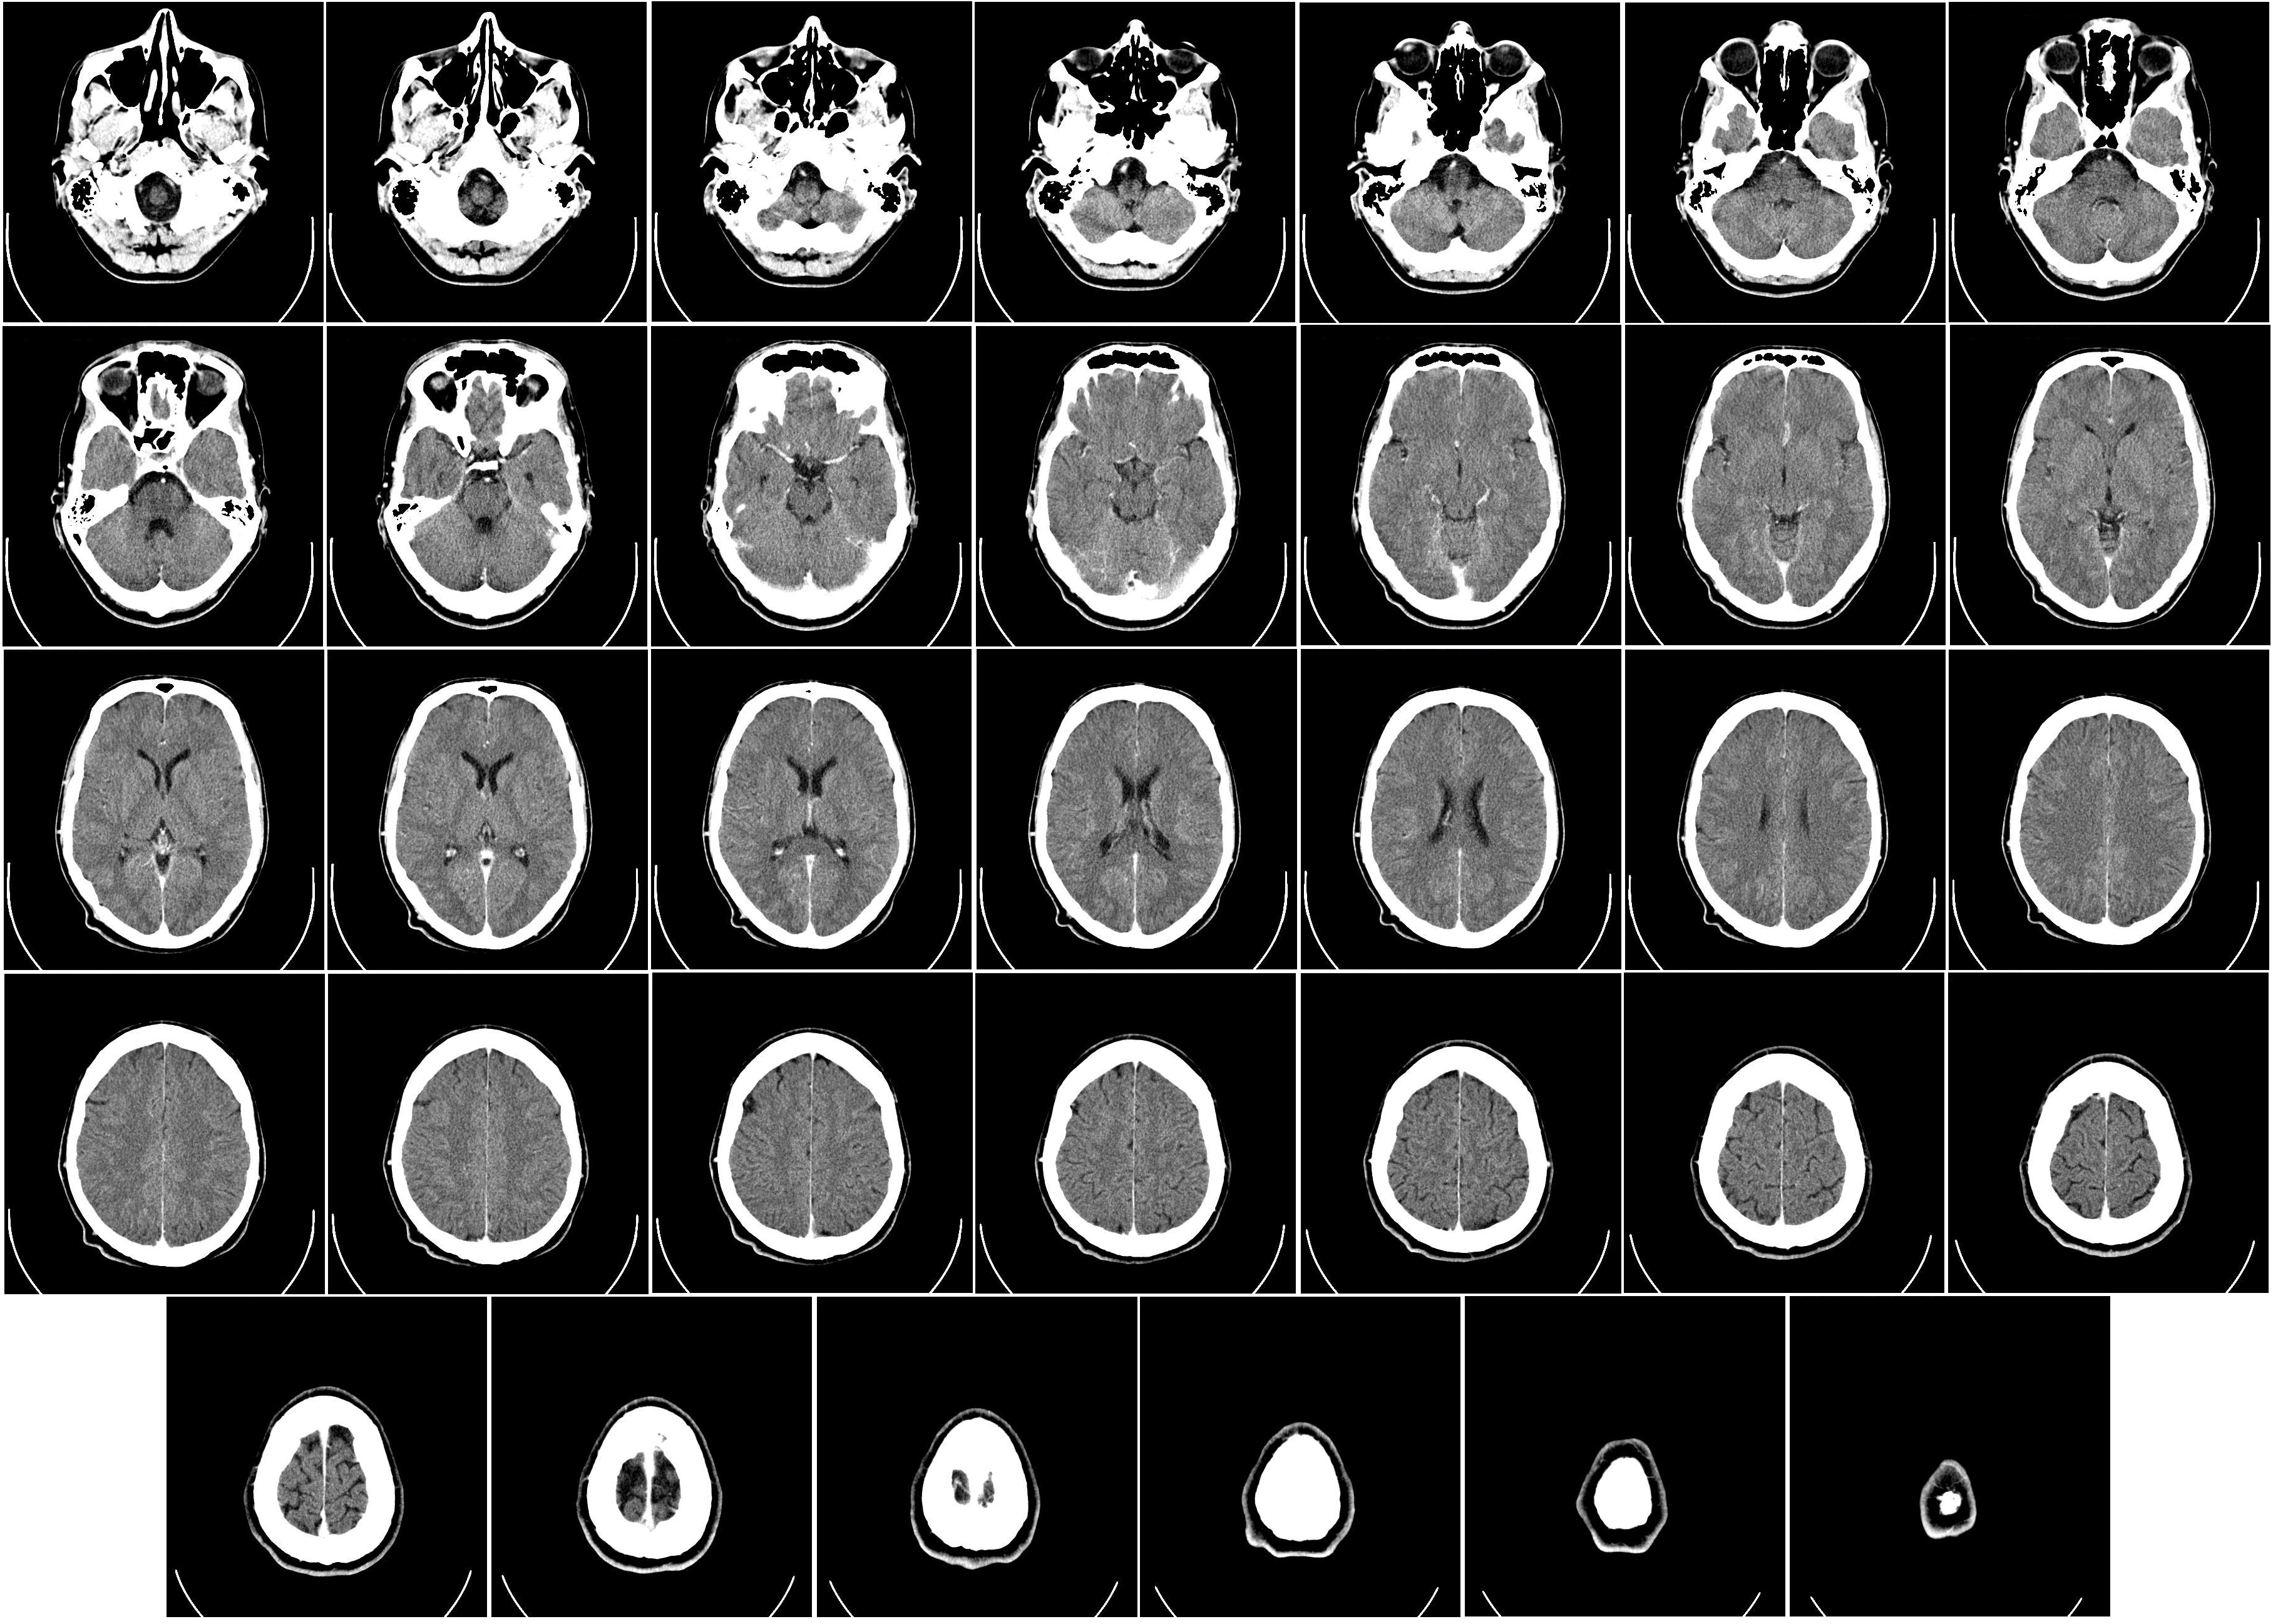

1971年10月1日,世界上第一台临床CT扫描仪在伦敦阿特金森·莫利医院(Atkinson Morley Hospital)安装完成。第一位接受CT扫描的患者是一位疑似脑肿瘤的女性。当医生们看到清晰显示的脑部结构和肿瘤位置时,所有人都被震撼了——这是人类历史上第一次在不开颅的情况下,清晰地看到大脑的内部结构。

1971年拍摄的第一张临床CT扫描图像,显示了额叶的囊性病变

正常人脑部CT横断面图像,可以清晰地分辨灰质、白质和脑脊液